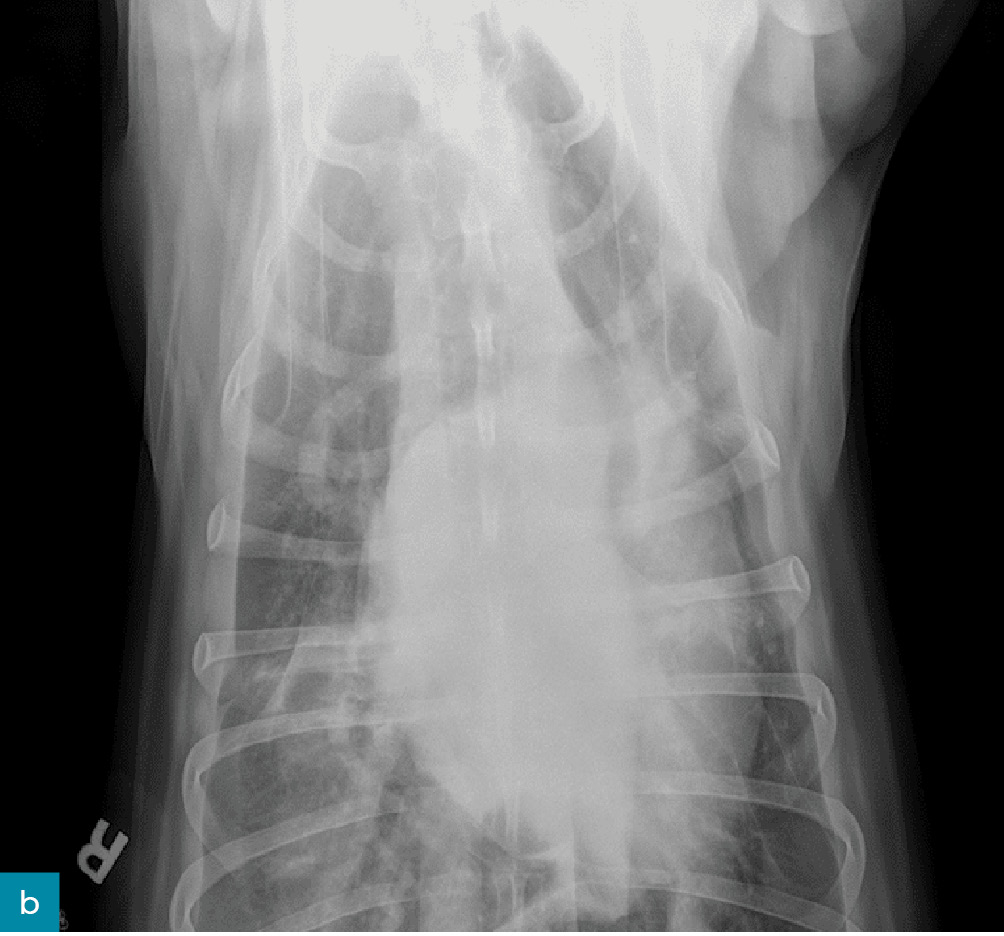

Lekarz weterynarii podstawowej opieki zdrowotnej poinformował, że badanie kliniczne pacjenta było w normie: temperatura wynosiła 38,2°C, częstość pracy serca 90 uderzeń/min, a częstość oddechów 35/min przy normalnym wysiłku. Odnotowano utratę masy ciała o 2 kg – podczas corocznego badania sześć miesięcy wcześniej wynosiła ona 33 kg. Wykonano przesiewowe badanie rentgenowskie jamy brzusznej oraz klatki piersiowej i zidentyfikowano płyn w przestrzeni opłucnowej (ryc. 2). Pacjent został skierowany do placówki specjalistycznej/ratunkowej w celu przeprowadzenia dodatkowej diagnostyki.

• Medium 1268

• Medium 1306

Ryc. 2. Prawe profilowe (a) i brzuszno-grzbietowe (b) zdjęcie klatki piersiowej pacjenta z chłonkopiersiem, pokazujące płyn w przestrzeni opłucnowej.

W ośrodku ratunkowym pacjent był ożywiony, czujny i reagował na bodźce. Stwierdzono szmer skurczowy serca stopnia 2/6. Radiogramy klatki piersiowej potwierdziły płyn w jamie opłucnej i wykazały łagodną niedodmę doogonowych pól płucnych. Podczas nakłucia klatki piersiowej usunięto około 3 ml białego, mlecznego płynu z lewej doczaszkowej części klatki piersiowej i około 20 ml z prawej części klatki piersiowej. Rodzaje płynu gromadzącego się w przestrzeni opłucnej obejmują przesięk, zmodyfikowany przesięk, wysięk oraz wysięk limfatyczny. Biorąc pod uwagę wygląd płynu, podejrzewano wysięk limfatyczny. Ostateczne rozpoznanie chłonkopiersia opiera się na wykryciu w płynie stężenia triglicerydów wyższego niż w surowicy. Płyn został przesłany wraz z krwią i moczem do badań diagnostycznych.